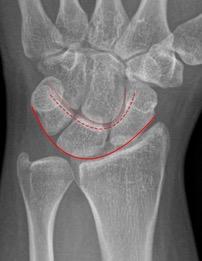

Perilunär luxation innebär en luxation mellan karpalben och lunatum. Missad skada slutar ofta med total handledsartrodes. För att upptäcka skadan på röntgen bör man leta efter oordning bland karpalbenen och avbrott i Gi lulas linjer som i normalfallet förlöper som två harmoniska bågar (se bild). Skadan framträder oftast tydligast på sidobilden med capitatums läge dorsalt beläget om lunatum. Obser vera medianusfunktionen och gör ett försök till sluten reposition. Patient en ska behandlas på operation med stiftning och ligamentsutur oavsett om repositionen lyckats eller ej.

Arvid von Konow Gilulas linjer ska löpa som två harmoniska bågar i carpallederna. Perilunär luxation ses oftast tydligast på sidobilden. Vid skada blir bågarna störda och svåra att följa. Vid Seymourfraktur genom fysen på distala falangen blir ofta nagelbädden nedslagen i frakturen.Läkning efter hälseneruptur sker i tre faser: